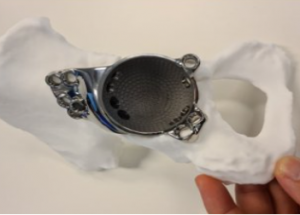

Es treballarà amb una mostra prevista de 180 pacients d’entre 18 i 80 anys dels set centres implicats, i aquests es dividiran en dos grups: un grup experimental tractat amb cirurgia digital 3D i un grup control tractat amb cirurgia convencional. Els procediments quirúrgics estudiats seran l’osteotomia de radi, una tècnica utilitzada per corregir malformacions del radi; l’artroplàstia acetabular de maluc, per tractar el desgast del maluc mitjançant la substitució dels components de l’articulació; i l’artròdesi de columna, que fusiona les vèrtebres per tractar dolor causat per fractures o malalties degeneratives.

Procés per tractar l’artroplàstia de maluc amb cirurgia digital 3D, des de la planificació digital 3D a la impressió 3D per crear un producte sanitari personalitzat.

En aquest sentit, segons afirma Fillat, la tecnologia 3D ha guanyat pes, especialment en cirurgia ortopèdica i traumatologia, perquè “permet crear models anatòmics exactes i guies quirúrgiques personalitzades a partir de les imatges del pacient, i simular digitalment el procediment quirúrgic, millorant la precisió i reduint els marges d’error”.